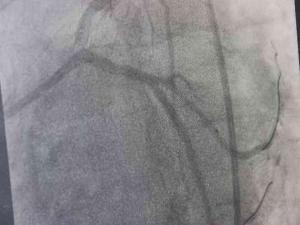

Trans yağların özelliklerinden dolayı endüstride son derece rağbet gördüğünü aktaran Doç. Dr. Akdağ, “Biz, istemiyoruz. Çünkü trans yağlar insan vücudundaki doğal yağ grubundan çok farklı. Trans yağlar özellikle damarın endotel dediğimiz en önemli kısmını bozan bir madde. Dolayısıyla trans yağlar damar yapılarını bozduğu için başta kalp ve beyin olmak üzere vücudun birçok organına zarar vermekte. Bununla beraber birçok kanserin oluşumuna yol açabilmekte. Obeziteye, şeker ve kolesterol değerlerimizi artırabilmekte. Bu nedenler dolayı biz, trans yağların kullanımını istemiyoruz. Trans yağlar 1911 yılında maalesef hayatımıza girdi. O günden bugüne giderek tüketimi artmakta” dedi.